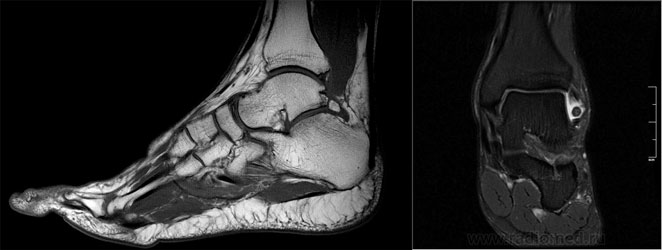

- Рентгенография. Самый важный диагностический параметр. Позволяет увидеть характерные неанатомические разрастания, имеющие вид шипов, крючков.

рентген голеностопного сустава. - КТ. Метод, позволяющий понять строение остеофитов. Также он помогает обнаружить патологию на начальной стадии, когда рентгена может быть недостаточно для постановки диагноза.

- Применяется для диагностики остеофитов в области голеностопного сустава, за исключением спорных случаев.

МРТ голеностопного сустава.